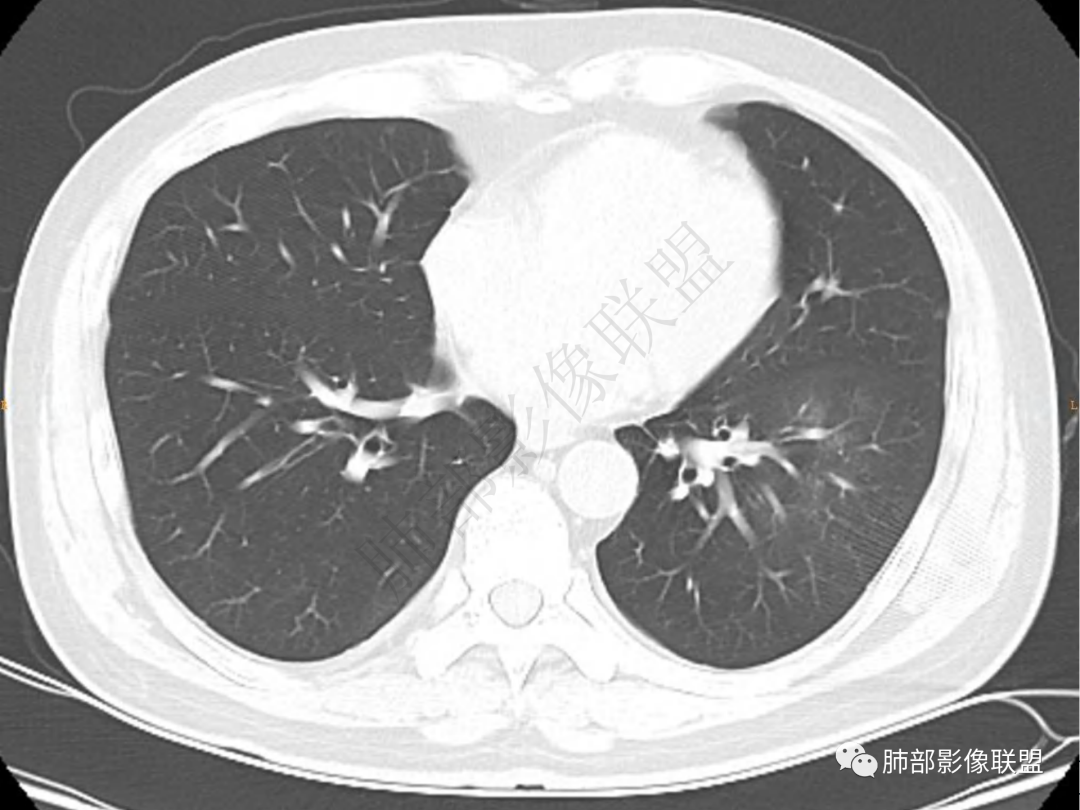

2.左肺下叶团片影,跨背段及内前基底段,实性部分类椭圆形,密度不甚均匀,可见毛刺及棘状突起,未见典型分叶及胸膜凹陷。病灶上下缘可见相应肺段支气管旁进侧出,管壁轻度增厚,未见狭窄阻塞。

3.周边较大范围磨玻璃影,边界相当模糊,小叶增厚明显。注意叶裂另一侧、左肺舌段亦可见磨玻璃影及增厚的小叶间隔。未见明确卫星病灶。

4.实性部分不均匀环形强化并显示一小范围低密度坏死区或空洞。较之肺窗,整体纵隔窗范围较小,提示病灶并不十分密实。抑或为不同时段图像。

5.双肺门及纵隔未见增大淋巴结。未见胸腔积液。